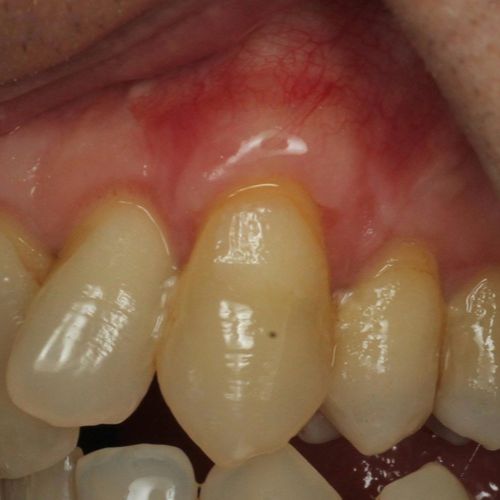

![]() | ![]() |

| Free gingival graft surgery’ to thicken gum and prevent further recession | Gum recession surgery in an aesthetic site |